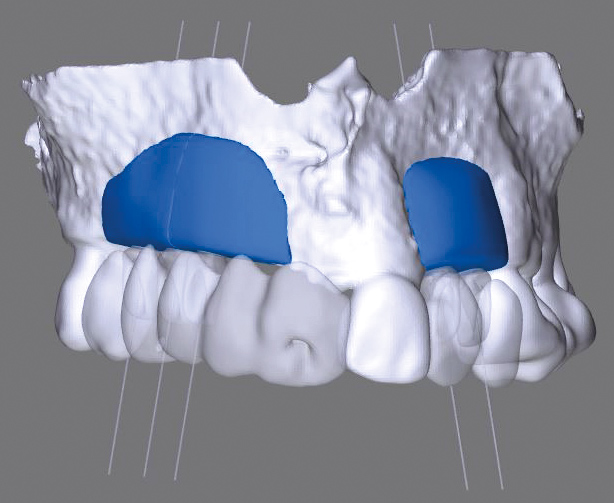

Model of the initial defect computed from a CBCT scan - buccal view